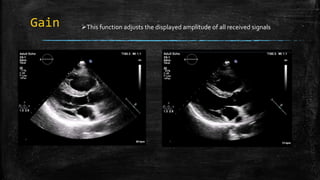

Gain This function adjusts the displayed amplitude of all received signals

Gain This functionadjusts the displayed amplitude of all received signals